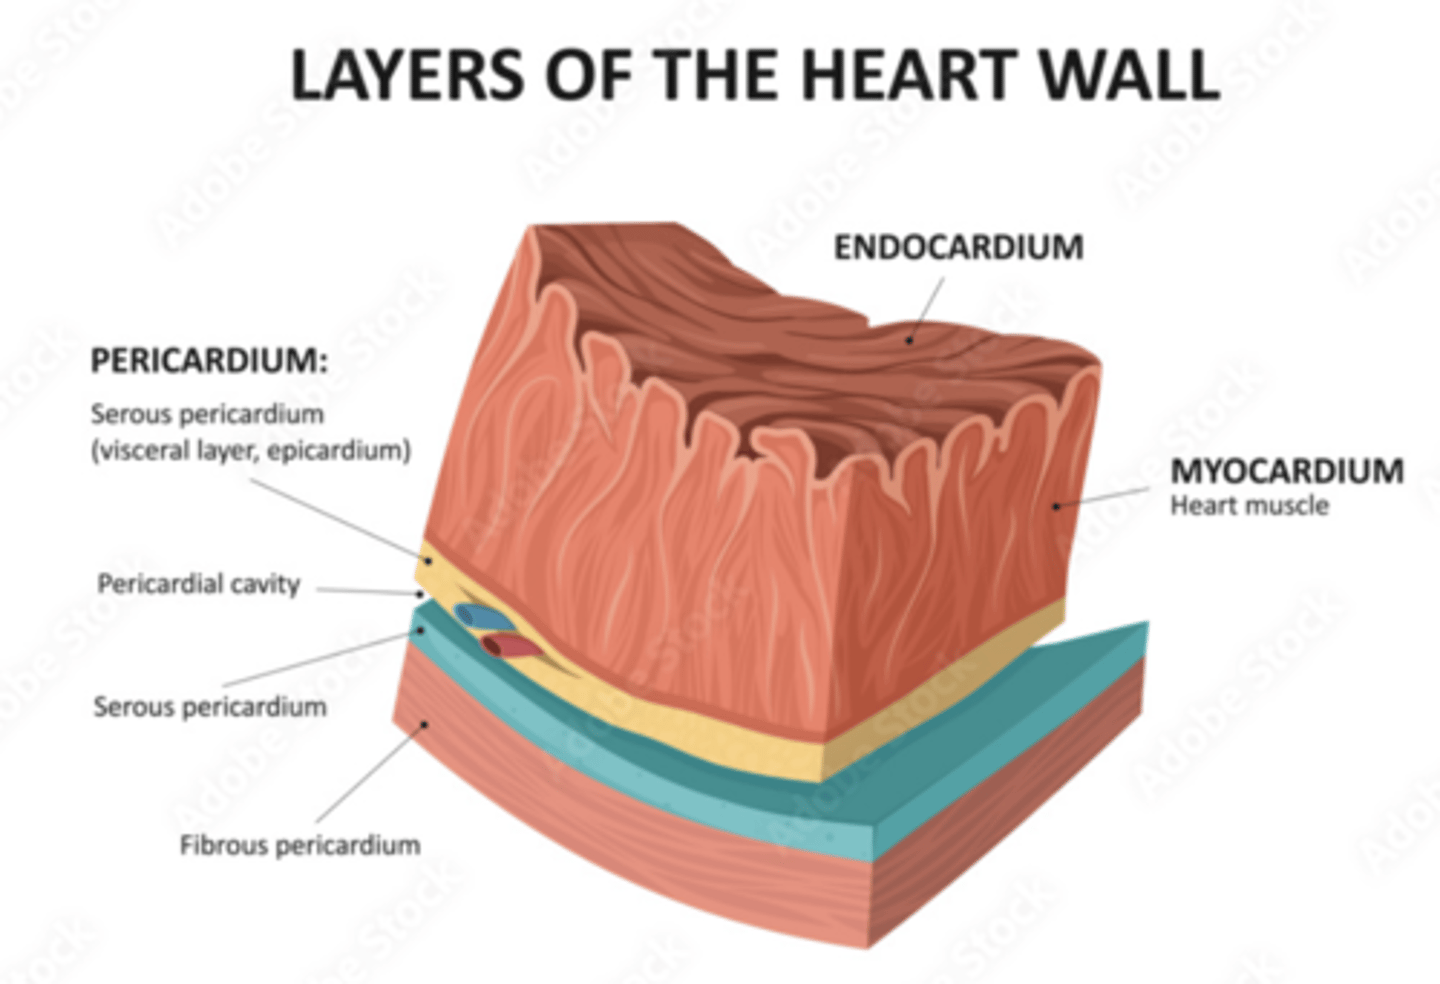

What are the layers of the pericardium?

The pericardium consists of two main layers:

- the fibrous pericardium

- the serous pericardium

How is divided the serous pericardium?

. Visceral layer or Epicardium (innermost). Adheres to the heart

. Parietal layer (outermost)

Between these layers is the pericardial fluid (pericardium cavity )

What is the fibrous pericardium?

the tough, outer layer

protects the heart

maintains its position in the thorax.

defines the boundaries of the medium mediastinum

What are the layers of the heart?

Epicardium: outermost covering.

Myocardium (right << left)

Endocardium or endothelium: inner thin layer of simple squamous epithelium